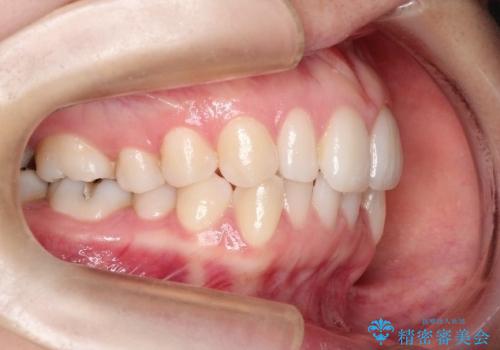

初診時の歯並びの状態としては、上下ともに前歯部の中等度のがたつきがあり、特に左上の前歯が1本内側に入り込んでしまっている状態でした。

また、2mm程度の正中離開がありました。

抜歯なし/インビザラインによるマウスピース矯正にて治療を行いました。

内側に入り込んでしまっている歯を出してくることに非常に時間がかかりましたが、一度歯を歯茎の方へ押し込みそして前へ出してくる2段階の治療を行いました。